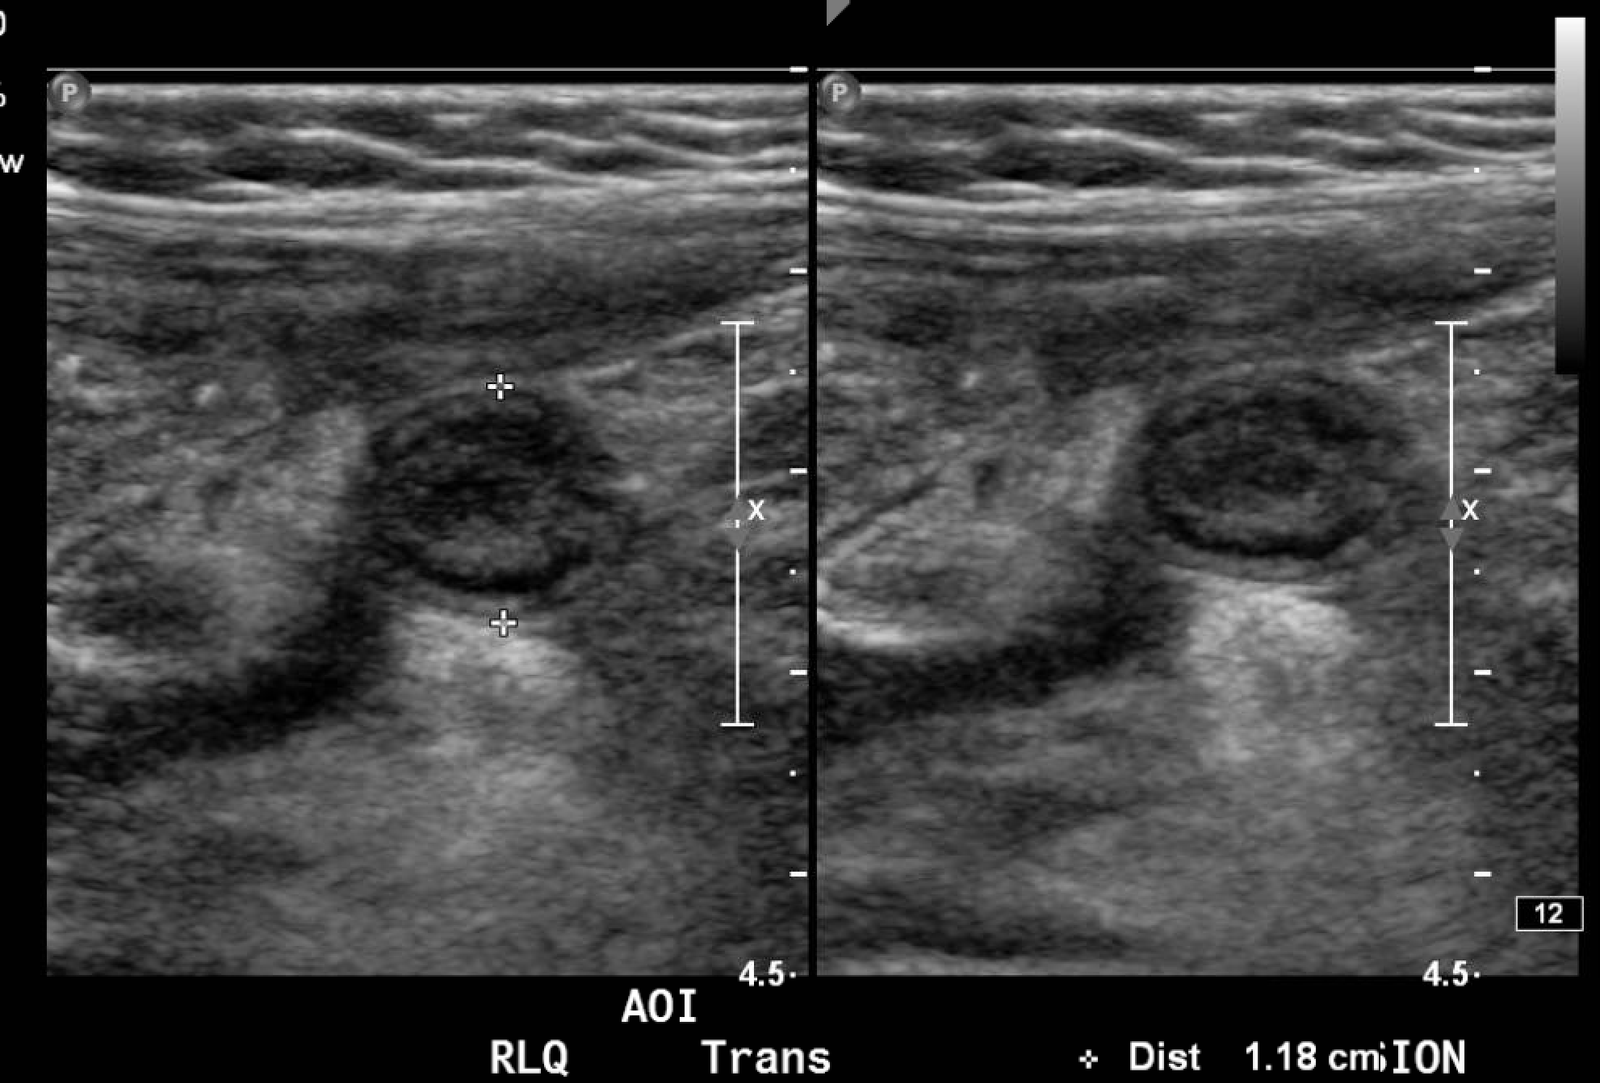

In the long axis video, the appendix appears as an enlarged, non-compressible, blind-ending tubular structure (white arrow) with distinct appendiceal wall layers and lack of peristalsis. In the short axis video, the appendix appears as a target sign (yellow arrow) between the abdominal and psoas muscles. The maximal outer diameter (MOD) measures 11.8mm and the appendix wall measures 0.17mm. There is trace adjacent free fluid and echogenic periappendiceal fat. Transverse axis video and image (red arrow) demonstrate that the appendix is not compressible. These findings are consistent with acute appendicitis.